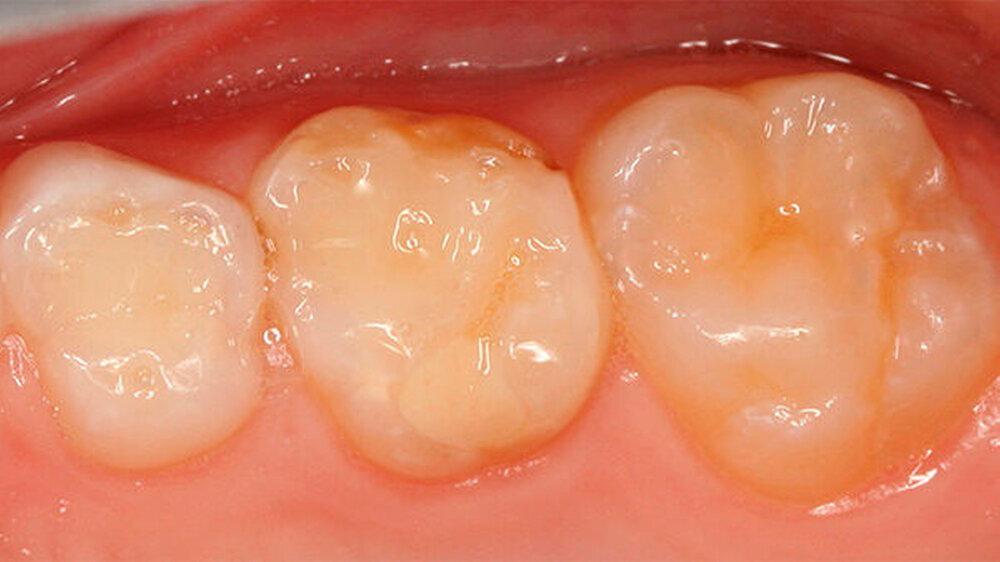

Zusätzlich zu den Frontzähnen waren die Molaren in sehr unterschiedlicher Ausprägung betroffen. Dies reichte von lediglich kleineren Opazitäten bis zu darüber hinausgehenden Schmelzverlusten: Im ersten Quadranten war Zahn 16 klinisch vollkommen unauffällig, hier zeigte aber der zweite Milchmolar insbesondere bukkal Opazitäten und Einbrüche des Schmelzes (Abbildungen 3 und 4) auf.

Zu ergänzen ist, dass die mesio-bukkale Opazität an Zahn 65 zwischen dem Zeitpunkt der Aufnahme der Patientin und der Präparation wenige Wochen später einen Einbruch der Schmelzoberfläche aufwies (Abbildungen 4 bis 6).